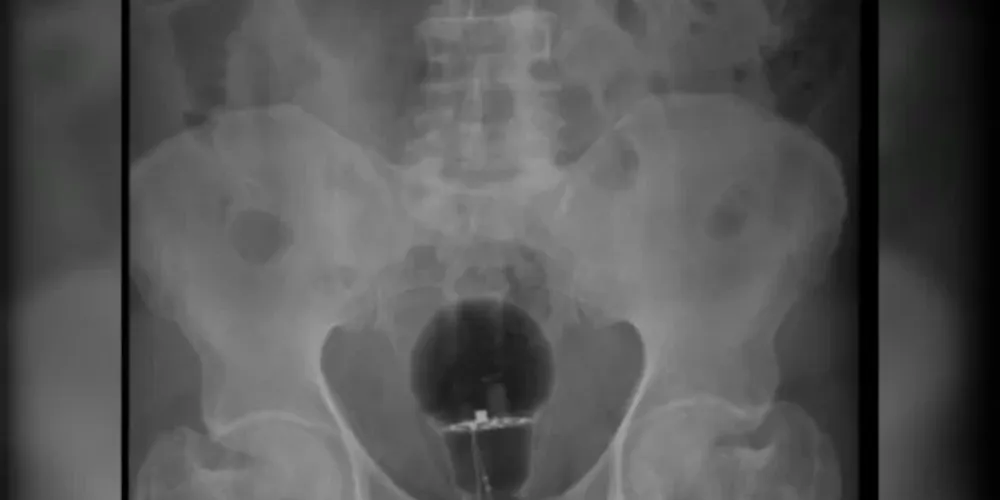

Um homem colombiano de 53 anos chegou a um hospital do país com dores intensas em março último. Aos médicos, o paciente disse não saber do que se tratava. No entanto, exames de imagem mostraram que uma lâmpada foi enfiada em seu reto.

“O objeto não era palpável ao toque”, afirmou o gastroenterologista Julian Pylori, que fez o atendimento, em um tweet. O médico usa as redes sociais com frequência para compartilhar atendimentos inusitados.

Objetos como este, que correm o risco de se quebrar, tem de ser retirados do corpo em procedimentos cirúrgicos. No entanto, segundo reportagem da TV Azteca, foi possível succionar a lâmpada porque ela era feita de plástico.